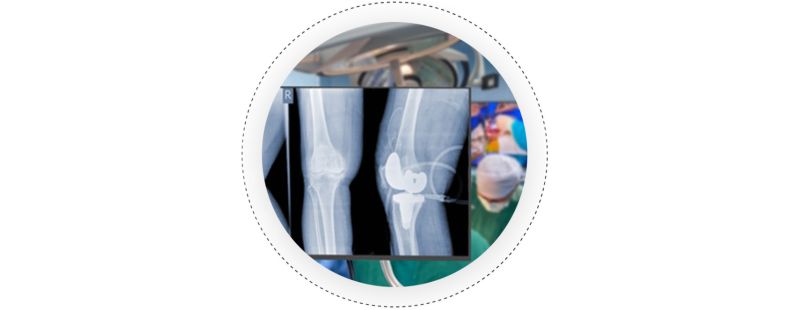

Joint Replacement Surgery

Joint replacement, which is also known as arthroplasty, is a surgical procedure that involves the removal of damaged or diseased parts of a joint. Following that, artificial implants made of metal, plastic, or ceramic materials are used to replace the removed parts. Joint replacement surgery can be conducted on various joints, including the hip, knee, shoulder, and elbow.